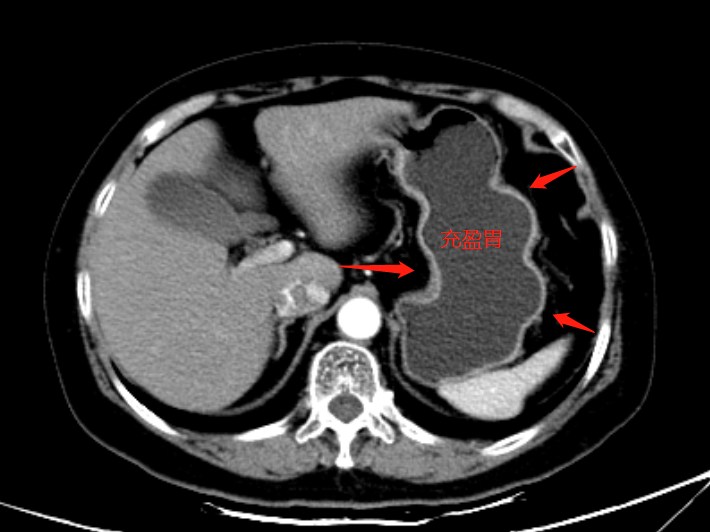

这些水经胃排入肠道,使肠道呈充盈状态,便于查看脏器类具体的病症。因为,做增强CT检查前需禁食4小时,此时人体的胃肠道处于收缩、聚拢状态,如果检查部位没有处于充盈状态,其显示的软组织密度和真正存在的软组织密度的病灶,无法进行确切的鉴别。